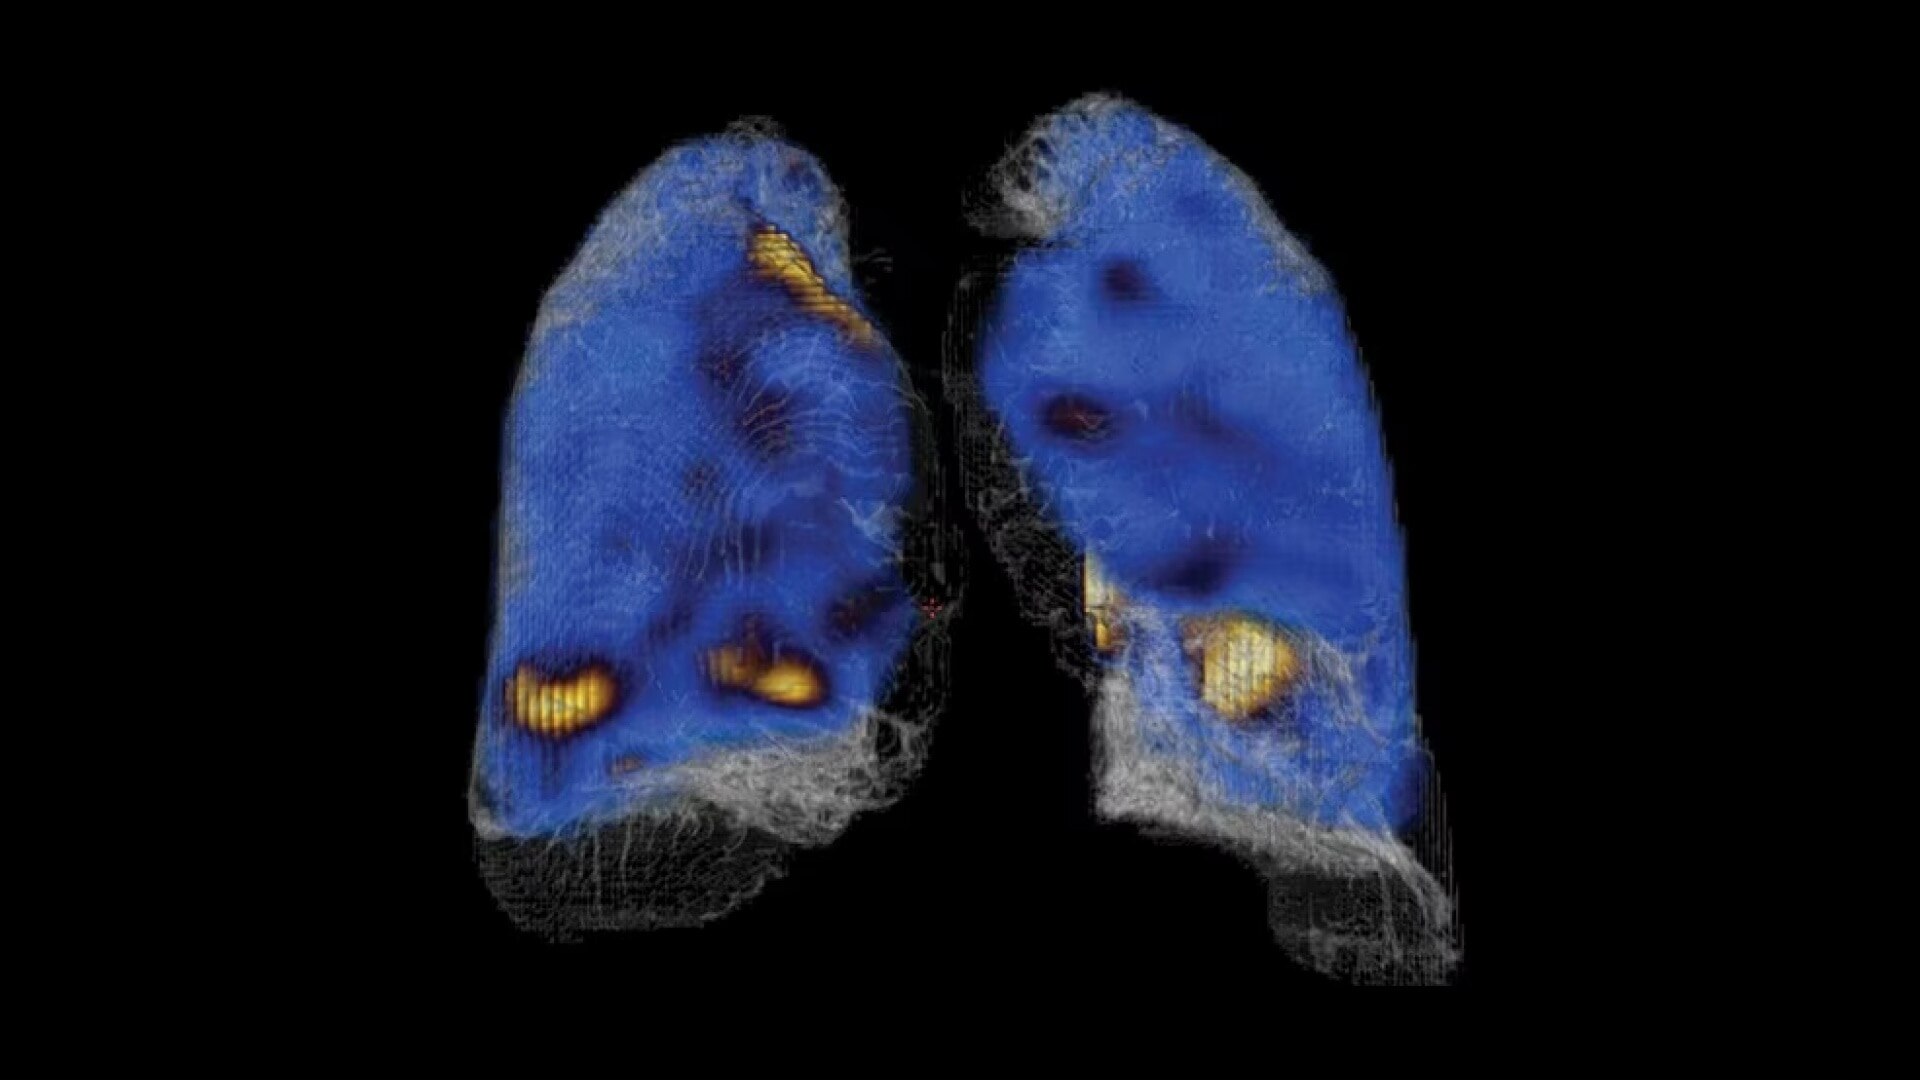

Full spectrum of SPECT/CT capability

In addition to the all-new SmartConsole, NM/CT 870 DR includes a new LEHRS (Low Energy High Resolution and Sensitivity) collimator, which can be combined with either SPECT Step & Shoot Continuous scanning mode or our Planar Clarity 2D processing to increase sensitivity and enable a reduction of scan time or injected dose². It's called SwiftScan Planar and SwiftScan SPECT.

NM/CT 870 DR includes our Elite NXT NM detectors, designed to address some of nuclear medicine’s biggest challenges. It also includes a 16-slice CT system with IQ Enhancement technology that enables helical coverage speed equivalent to that of a CT scanner at the same table speed³ with a 50-slice wider detector.

These improvements to both SPECT and CT technology are the foundation for quantitative results.